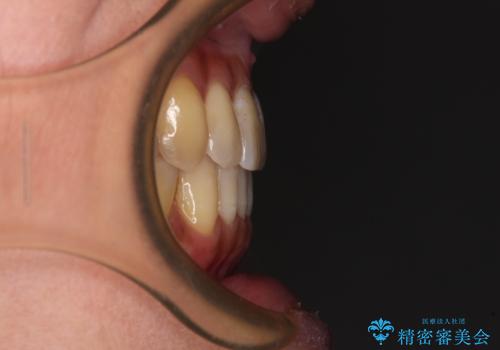

- 前歯のクロスバイトが気になり、インビザラインによる矯正治療を希望して来院された患者様です。

上顎側切歯(上の真ん中から2番目の歯)が舌側転位している場合、インビザラインでは仕上げきれないことが多く、更には無理して動かそうとすると歯髄壊死を起こすリスクが高いと言われています。

インビザラインで歯列を移動する前に、上顎前歯をワイヤー矯正で整え、その後上下歯列をインビザラインにて矯正治療を行うこととしました。

舌側転位している側切歯特有の、切縁の位置が不揃いであったり、根元が内側に引っ込んだ状態であったりという、インビザライン独特の仕上がりになることなく、きれいに整った歯列とすることができました。